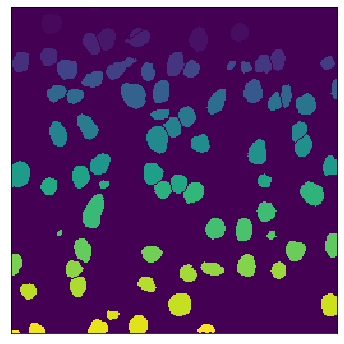

The field of computational pathology has witnessed great advancements since deep neural networks have been widely applied. These deep neural networks usually require large numbers of annotated data to train vast parameters. However, it takes significant effort to annotate a large histopathology dataset. We propose to build a data-efficient model, which only requires partial annotation, specifically on isolated nucleus, rather than on the whole slide image. It exploits shallow features as its backbone and is light-weight, therefore a small number of data is sufficient for training. What's more, it is a generative compositional model, which enjoys interpretability in its prediction. The proposed method could be an alternative solution for the data-hungry problem of deep learning methods.